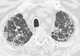

Pleuropulmonary fibrosis at lung apex